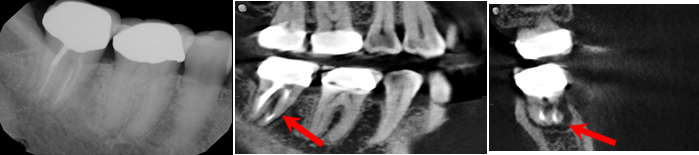

I came across a patient who was experiencing gingival pain in the lower right quadrant. Tooth number 31 was endodontically treated. A 2D digital image was taken, and the doctor found no obvious concerns. The patient was referred to the dental imaging center where I am employed, and we did a 3D cone beam CT scan. The CT results showed bone loss on the mesial wall and through the furcation of tooth number 31.